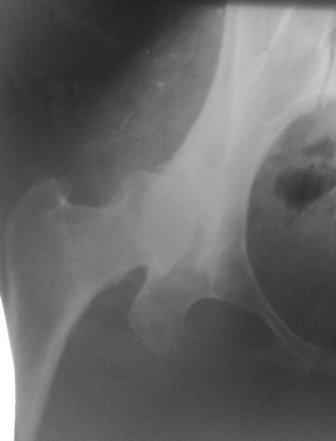

При более сохранном суставе от дальнейшего разрушения можно было бы сохранить только периориентацией нагрузки на сустав - Периацетабулярной Остеотомией .

Данный сустав в начальной стадии разрушения, но все-таки я бы сделал обзорный таз и отдельные снимки сустава в 30 градусной абдукции и аддукции. Также снимки с внутренней и наружной ротацией для оценки состояния головки бедра.